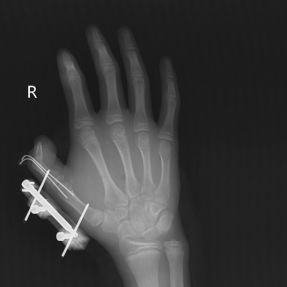

术后X线检查显示骨折复位良好

接诊的医生发现,维维右手拇指虎口撕开一道约10cm的伤口,伤口深可见骨、肌肉组织断裂外露,同时伴有拇指骨折、关节脱位,拇指已完全失去知觉。手足显微外科团队立即为他开通绿色通道,急诊手术清创、复位脱位的拇指掌指关节、固定骨折、逐层修复肌肉,术后经过医护团队7天的精心护理,维维的拇指虽然保住了,但需持续进行康复训练恢复手部精细动作功能。病床上的维维懊悔不已:“早知道干冰这么危险,我绝对不会去玩。”经过恢复,维维已出院。